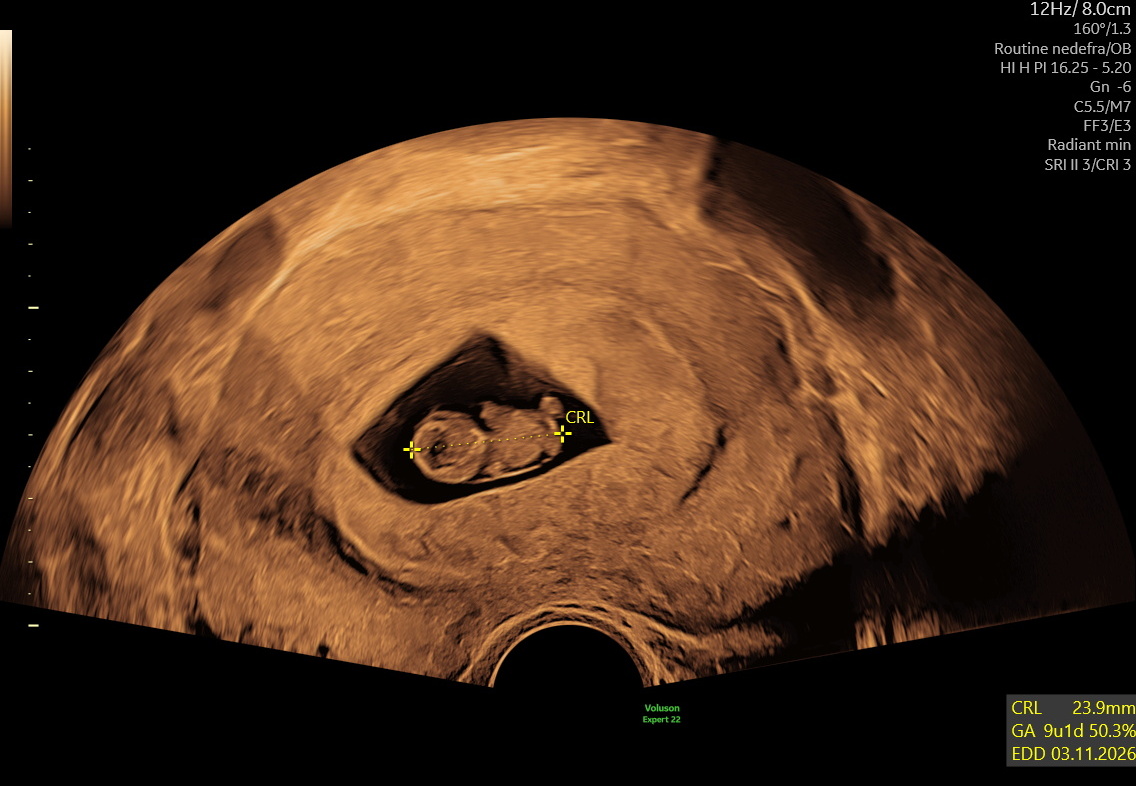

Tidlig scanning i Hillerød hos Centrumlægerne. Scanningen udføres af autoriserede jordemødre i tæt samarbejde med klinikkens læger. Vi bekræfter graviditeten, vurderer placering og udvikling og viser hjerteblink, når det er muligt.

En tidlig scanning er en ultralydsundersøgelse i starten af graviditeten, hvor vi afklarer de vigtigste forhold:

- Om graviditeten er korrekt placeret i livmoderen

- Om der er hjerteaktivitet

- Om der er ét eller flere fostre

- Estimering af hvor langt du er i graviditeten

Scanningen udføres vaginalt frem til uge 10+0 og derefter udvendigt. Fra uge 6–7 kan hjerteblink som regel ses tydeligt.